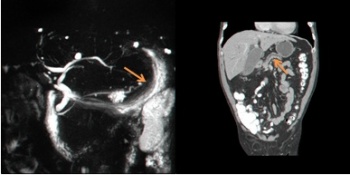

- צילום דרכי מרה בעזרת תהודה מגנטית (Magnetic resonance cholangiopancreatography - MRCP): בדיקה זו היא הרגישה מבין הבדיקות לזיהוי נגעים בלבלב ובצינורות הלבלב. מאז הוכנסה לשימוש חל שיפור משמעותי ביכולת האבחון של נגעים בלבלב.

בכל הבדיקות האלו נראה הרחבה של צינור הלבלב הראשי או באחד הענפים שלו. במקרים מסוימים שאיבה במחט עדינה (FNA) תאשר את האבחנה.